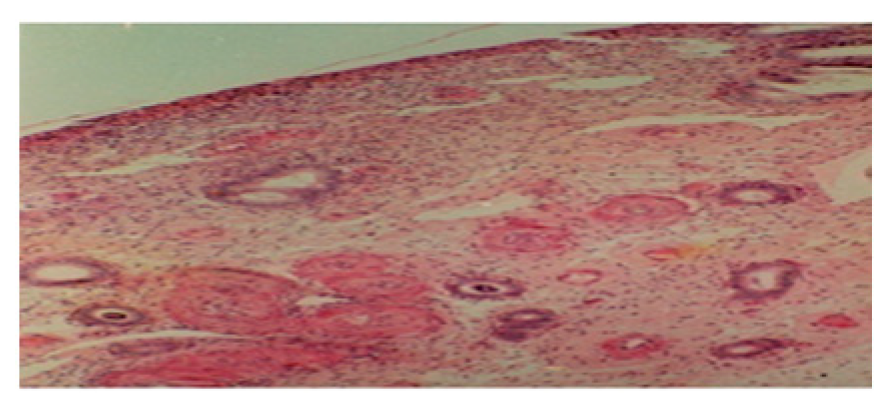

3.6. From 19th to 21st Postpartum Day

At the end of the third week at magnification (10) (Figure 6a), the surface epithelium appears to be more intact, uniform, and continuous over its entire surface.

Figure 6.

(a) Histological section of the endometrium between the nineteenth and twenty-first days postpartum(10). (b) Histological section of the endometrium between the nineteenth and twenty-first days postpartum (40).

At the highest magnification (40) (Figure 6b), the epithelium appears to be simple and cylindrical. In light of the histological results of the endometrium, it appears that uterine involution in camels completes on the 21st postpartum day. These results agree with those in Ref. [7], which reports a duration of 40 days. We also used the method of transrectal palpation. Our results are in agreement with those declared by the authors of Refs. [4,8], who reported a duration from 15 to 28 days. The uterine lining is completely restored from the 18th postpartum day.

The process of uterine involution occurs through the association of endometrial regeneration phenomena and vascular phenomena.